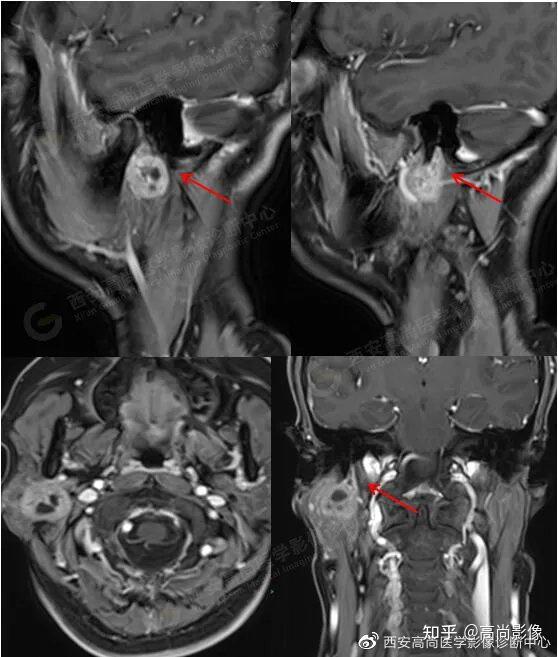

西安高尚医学影像病例腮腺区面神经鞘瘤

图片尺寸558x657